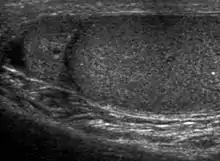

Fig. 21. Tuberculous epididymo-orchitis. (a) Transverse sonography of a surgically proved tuberculous epididymitis shows an enlarged epididymis containing calcification and necrosis. (b) Composite image: Transverse sonography of the same patient shows multiple hypoechoic nodules in the left testis associated with surrounding reactive hydrocele.

Although the genitourinary tract is the most common site of extra-pulmonary involvement by tuberculosis, tuberculous infection of the scrotum is rare and occurs in approximately 7% of patients with tuberculosis. At the initial stage of infection, the epididymis alone is involved. However, if appropriate antituberculous treatment is not administered promptly, the infection will spread to the ipsilateral testis. The occurrence of isolated testicular tuberculosis is rare. Clinically patients with tuberculous epididymo-orchitis may present with painful or painless enlargement of the scrotum, hence they cannot be distinguished from lesions such as testicular tumor, testicular infarction and may mimic testicular torsion.

At ultrasound, tuberculous epididymitis is characterized by an enlarged epididymis with variable echogenicity. The presence of calcification, caseation necrosis, granulomas and fibrosis can result in heterogeneous echogenicity [Fig. 21a]. The ultrasound findings of tuberculous orchitis are as follow: (a) diffusely enlarged heterogeneously hypoechoic testis (b) diffusely enlarged homogeneously hypoechoic testis (c) nodular enlarged heterogeneously hypoechoic testis and (d) presence of multiple small hypoechoic nodules in an enlarged testis [Fig. 21b].

Although both bacterial and tuberculous infections may involve both the epididymis and the testes, an enlarged epididymis with heterogeneously hypoechoic pattern favors a diagnosis of tuberculosis (Muttarak and Peh, 2006, as cited in Kim et al., 1993 and Chung et al., 1997). With color Doppler ultrasound, a diffuse increased blood flow pattern is seen in bacterial epididymitis, whereas focal linear or spotty blood flow signals are seen in the peripheral zone of the affected epididymis in patients with tuberculosis.